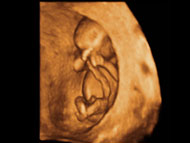

Met 10-12 weken gaat u echt een kindje herkennen, alles zit er dan in principe op en aan. Het kindje beweegt op dit moment vrij veel in de baarmoeder en we noemen het kindje dan ook wel een ‘jumping foetus’. Deze bewegingen zijn echt geweldig om te zien! Een voorbeeld van een kindje rond deze periode in 3D kunt u zien op foto 2, u ziet hier het kindje verbonden aan zijn navelstreng mooi in de holte van de baarmoeder liggen.

Foto 2